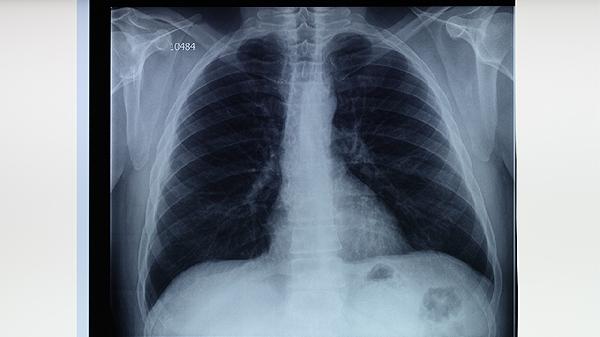

肺高密度结节通常无明显症状,多数在体检时偶然发现。部分患者可能出现咳嗽、胸痛、咯血、呼吸困难等表现,可能与炎症、结核、肿瘤等因素有关。建议及时就医明确性质。

多数肺高密度结节体积较小且位置局限,早期不会引起明显不适。这类结节常见于良性病变如钙化灶、陈旧性结核灶或错构瘤,通常通过胸部CT随访观察即可。若结节形态规则、边缘光滑且长期稳定,恶性概率较低。